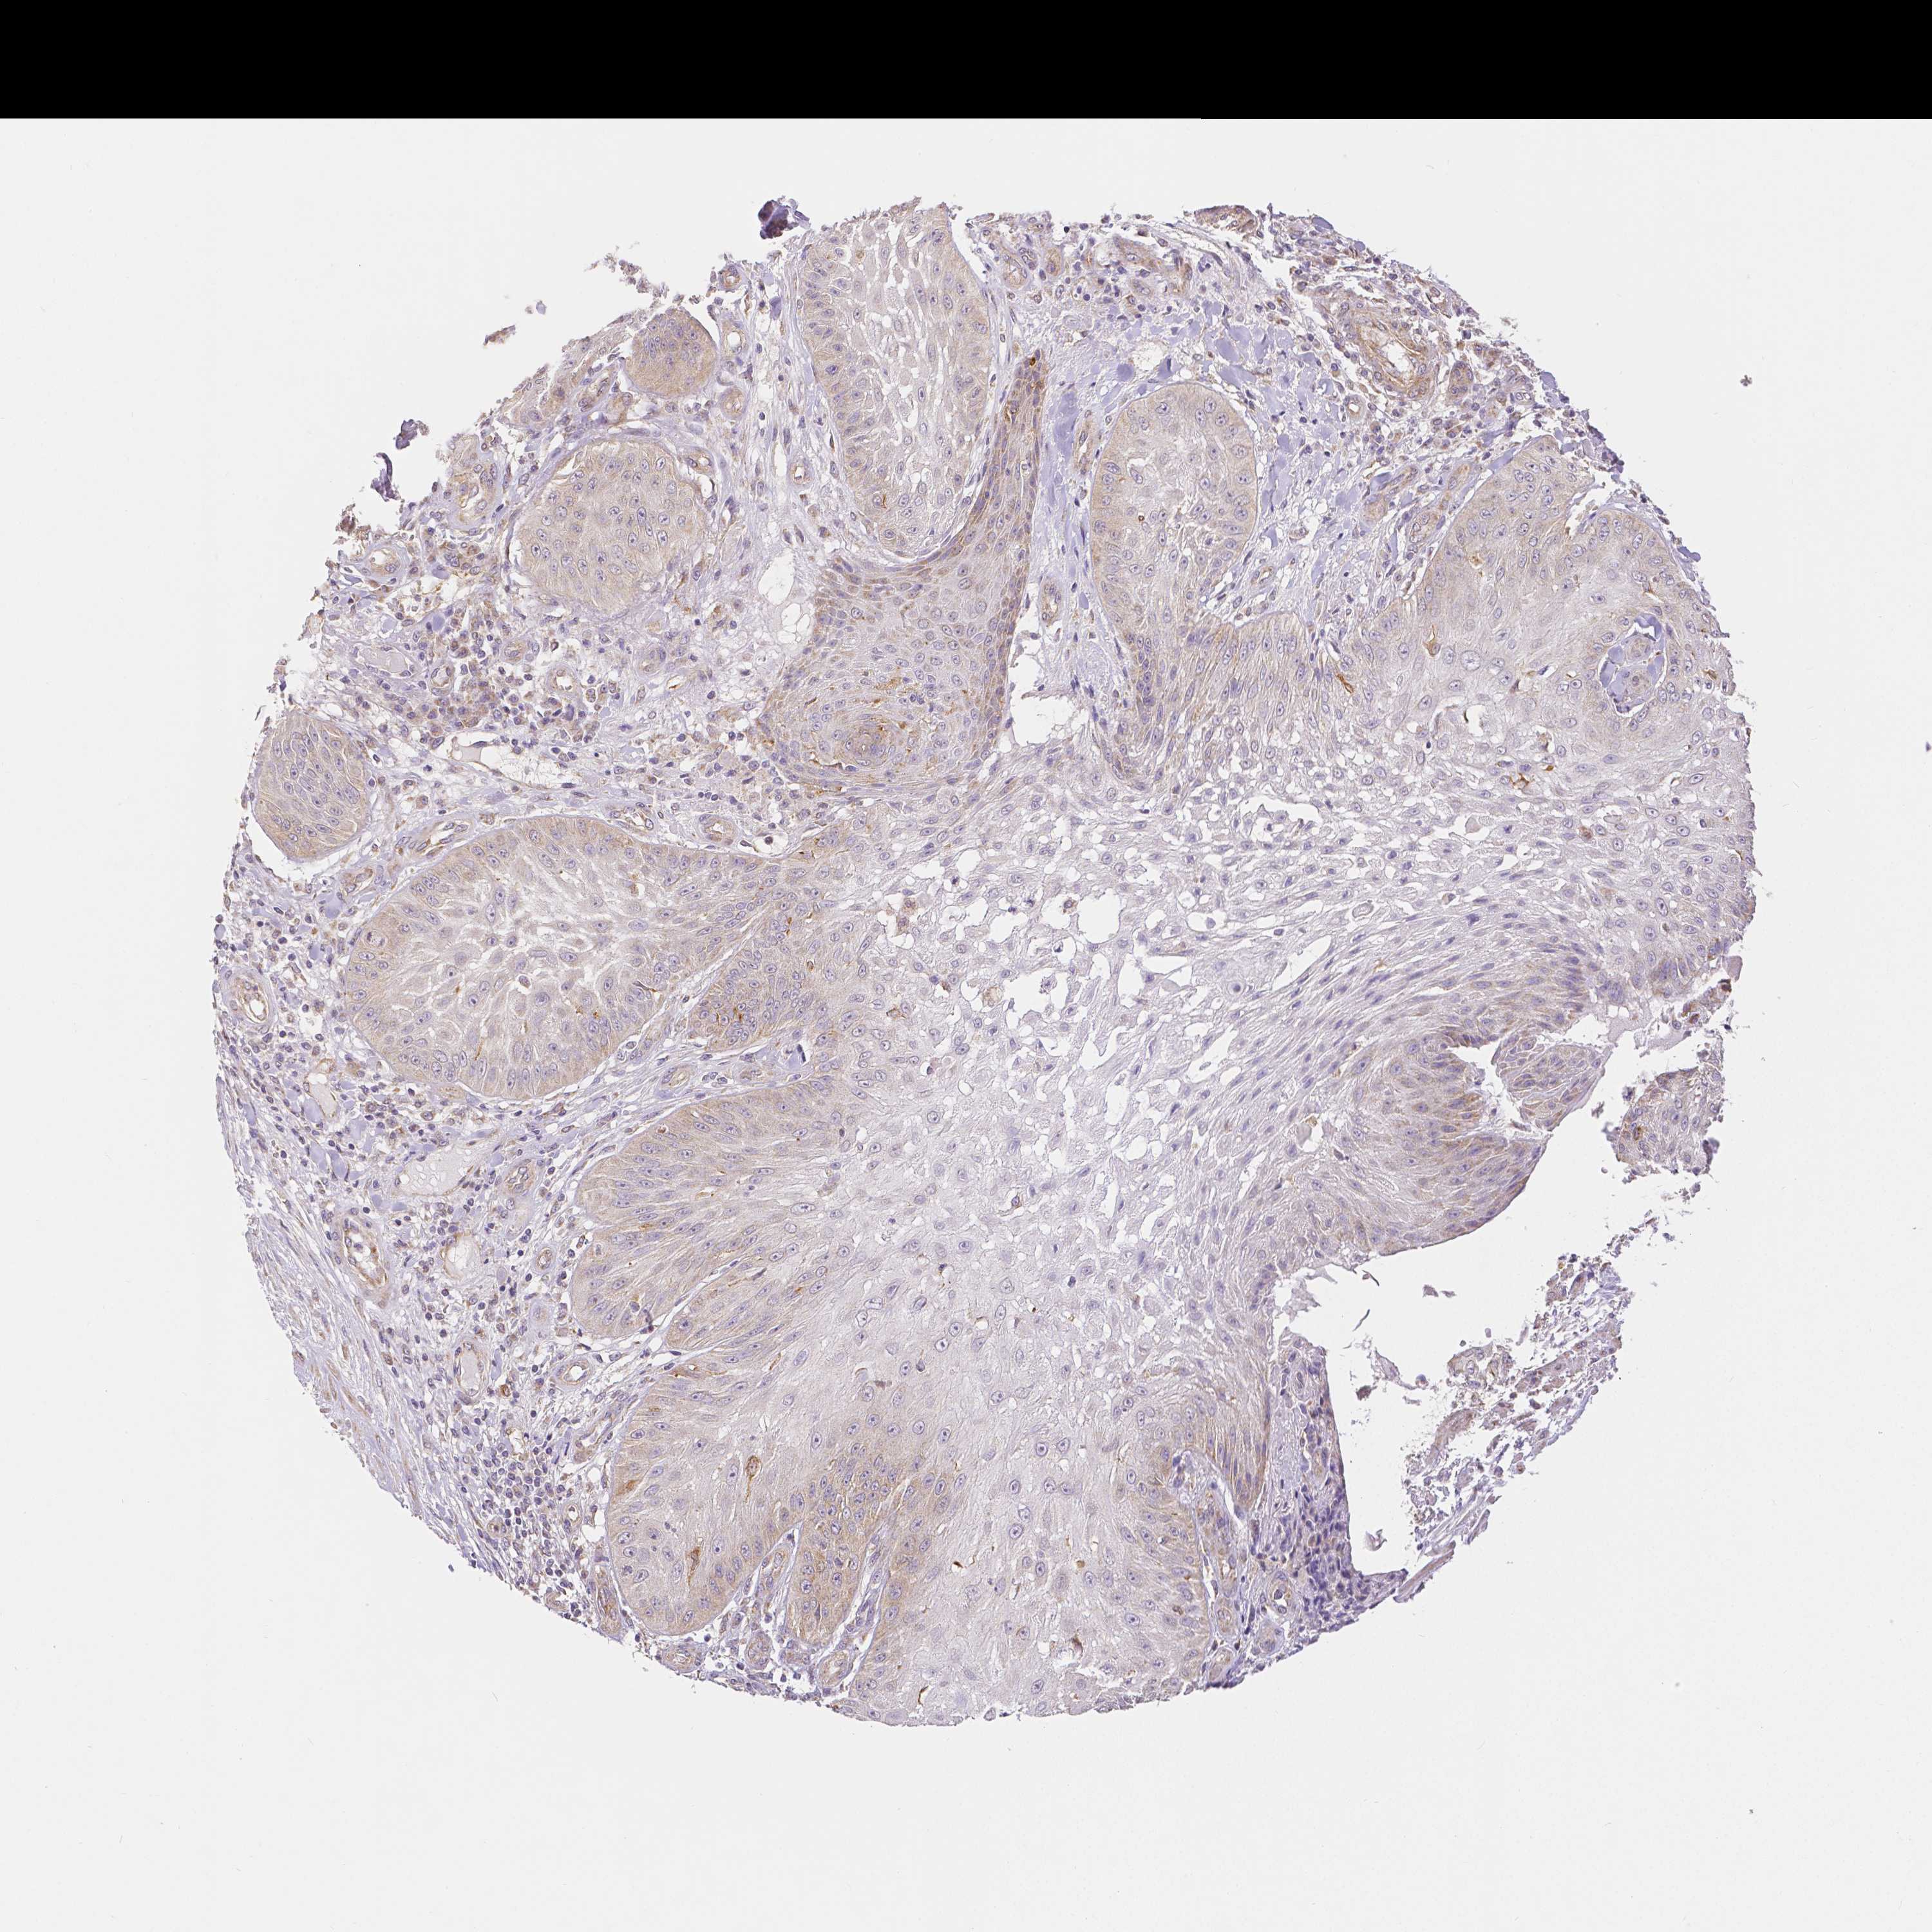

CANCER SKIN CANCER Show tissue menu

Basal cell and squamous cell cancer

SKIN CANCER - Protein expressioni

A mouse-over function shows sample information and annotation data. Click on an image to view it in a full screen mode. Samples can be filtered based on level of antibody staining by selecting one or several of the following categories: high, medium, low and not detected. The assay and annotation is described here.

Each image is clickable and will lead to virtual microscopy that enables deeper exploration of all samples and also displays staining intensity scores, fraction scores and subcellular localization as well as patient and tissue information for each sample.

Antibody HPA010687

Squamous cell carcinoma, NOS

Squamous cell carcinoma, metastatic, NOS

Basal cell carcinoma

Papilloma, NOS